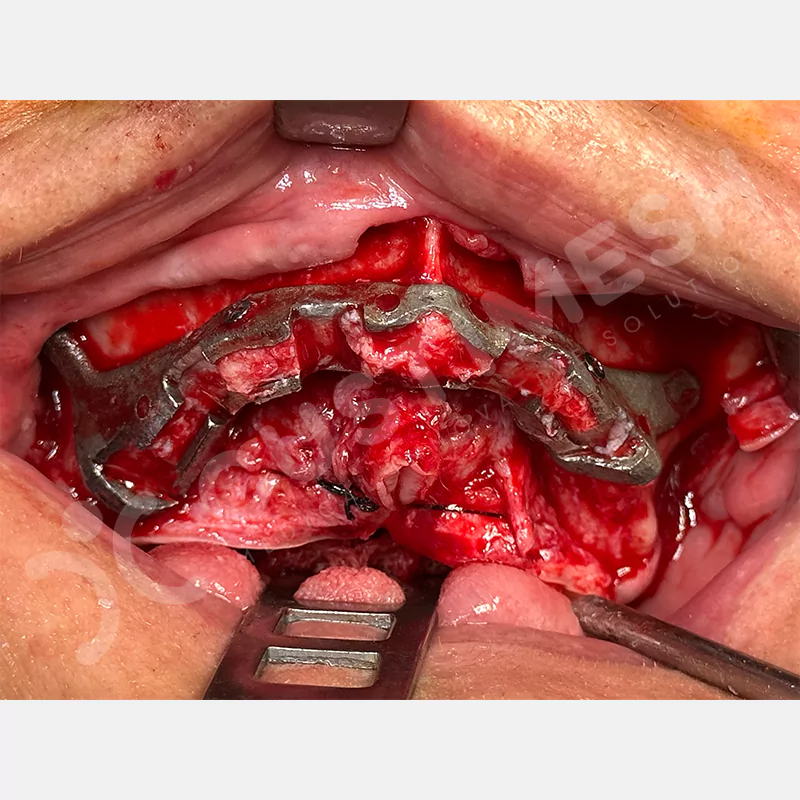

Modern diş hekimliğinde, çene gelişimini tamamlamamış veya ciddi kemik kaybı yaşayan hastalar için kişiye özel titanyum implantlar ile çözüm bulunmaktadır. CAD/CAM teknolojisi ve lazer sinterleme yöntemiyle üretilen bu implantlar, hastanın bireysel anatomik yapısına tam uyum sağlayarak geleneksel implantların uygulanamadığı vakalarda mükemmel bir alternatif oluşturmaktadır. Özellikle ileri derecede kemik kaybı olan hastalar için geliştirilen subperiosteal implantlar, periostun altına yerleştirilerek minimal invaziv bir yaklaşım sunarken, bilgisayarlı tomografi verileri ve sonlu eleman analizleriyle optimize edilmiş tasarımları sayesinde hem estetik hem de fonksiyonel sonuçlar garanti etmektedir. Bu yenilikçi teknoloji, tek seansta implant ve protez uygulamasına imkan vererek hastaların aynı gün doğal gülüşlerine kavuşmalarını sağlarken, kemik greftleme gibi ek işlem ihtiyacını ortadan kaldırarak cerrahi süreci büyük ölçüde kolaylaştırmaktadır. Kişiye özel tasarımı ve üstün biyouyumluluğu sayesinde, daha önce tedavisi mümkün görülmeyen kompleks vakalarda bile başarılı sonuçlar sunan bu implantlar, modern diş hekimliğinde yeni bir çağ açarak hastaların yaşam kalitesini artırmayı hedeflemektedir.

VAKA 1

VAKA 2

VAKA 3

VAKA 4